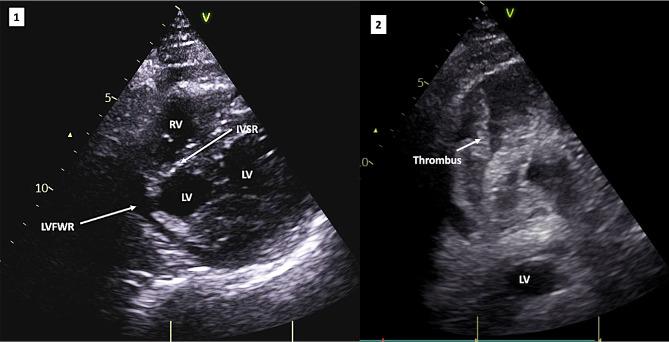

Left ventricular free wall rupture (LVFWR) and interventricular septal rupture (VSR) are potentially catastrophic mechanical complications after acute myocardial infarction (AMI). When they occur together, "double myocardial rupture" (DMR), survival is unlikely. DMR is seen in only 0.3% of all AMIs. With or without surgical intervention, the odds are against the patient.

左心室游离壁破裂(LVFWR)和室间隔破裂(VSR)是急性心肌梗死(AMI)后潜在的灾难性机械并发症。当它们同时发生时,称为“双心肌破裂”(DMR),患者几乎不可能存活。DMR 仅见于所有 AMI 的 0.3%。无论是否进行手术干预,患者的存活几率都很小。